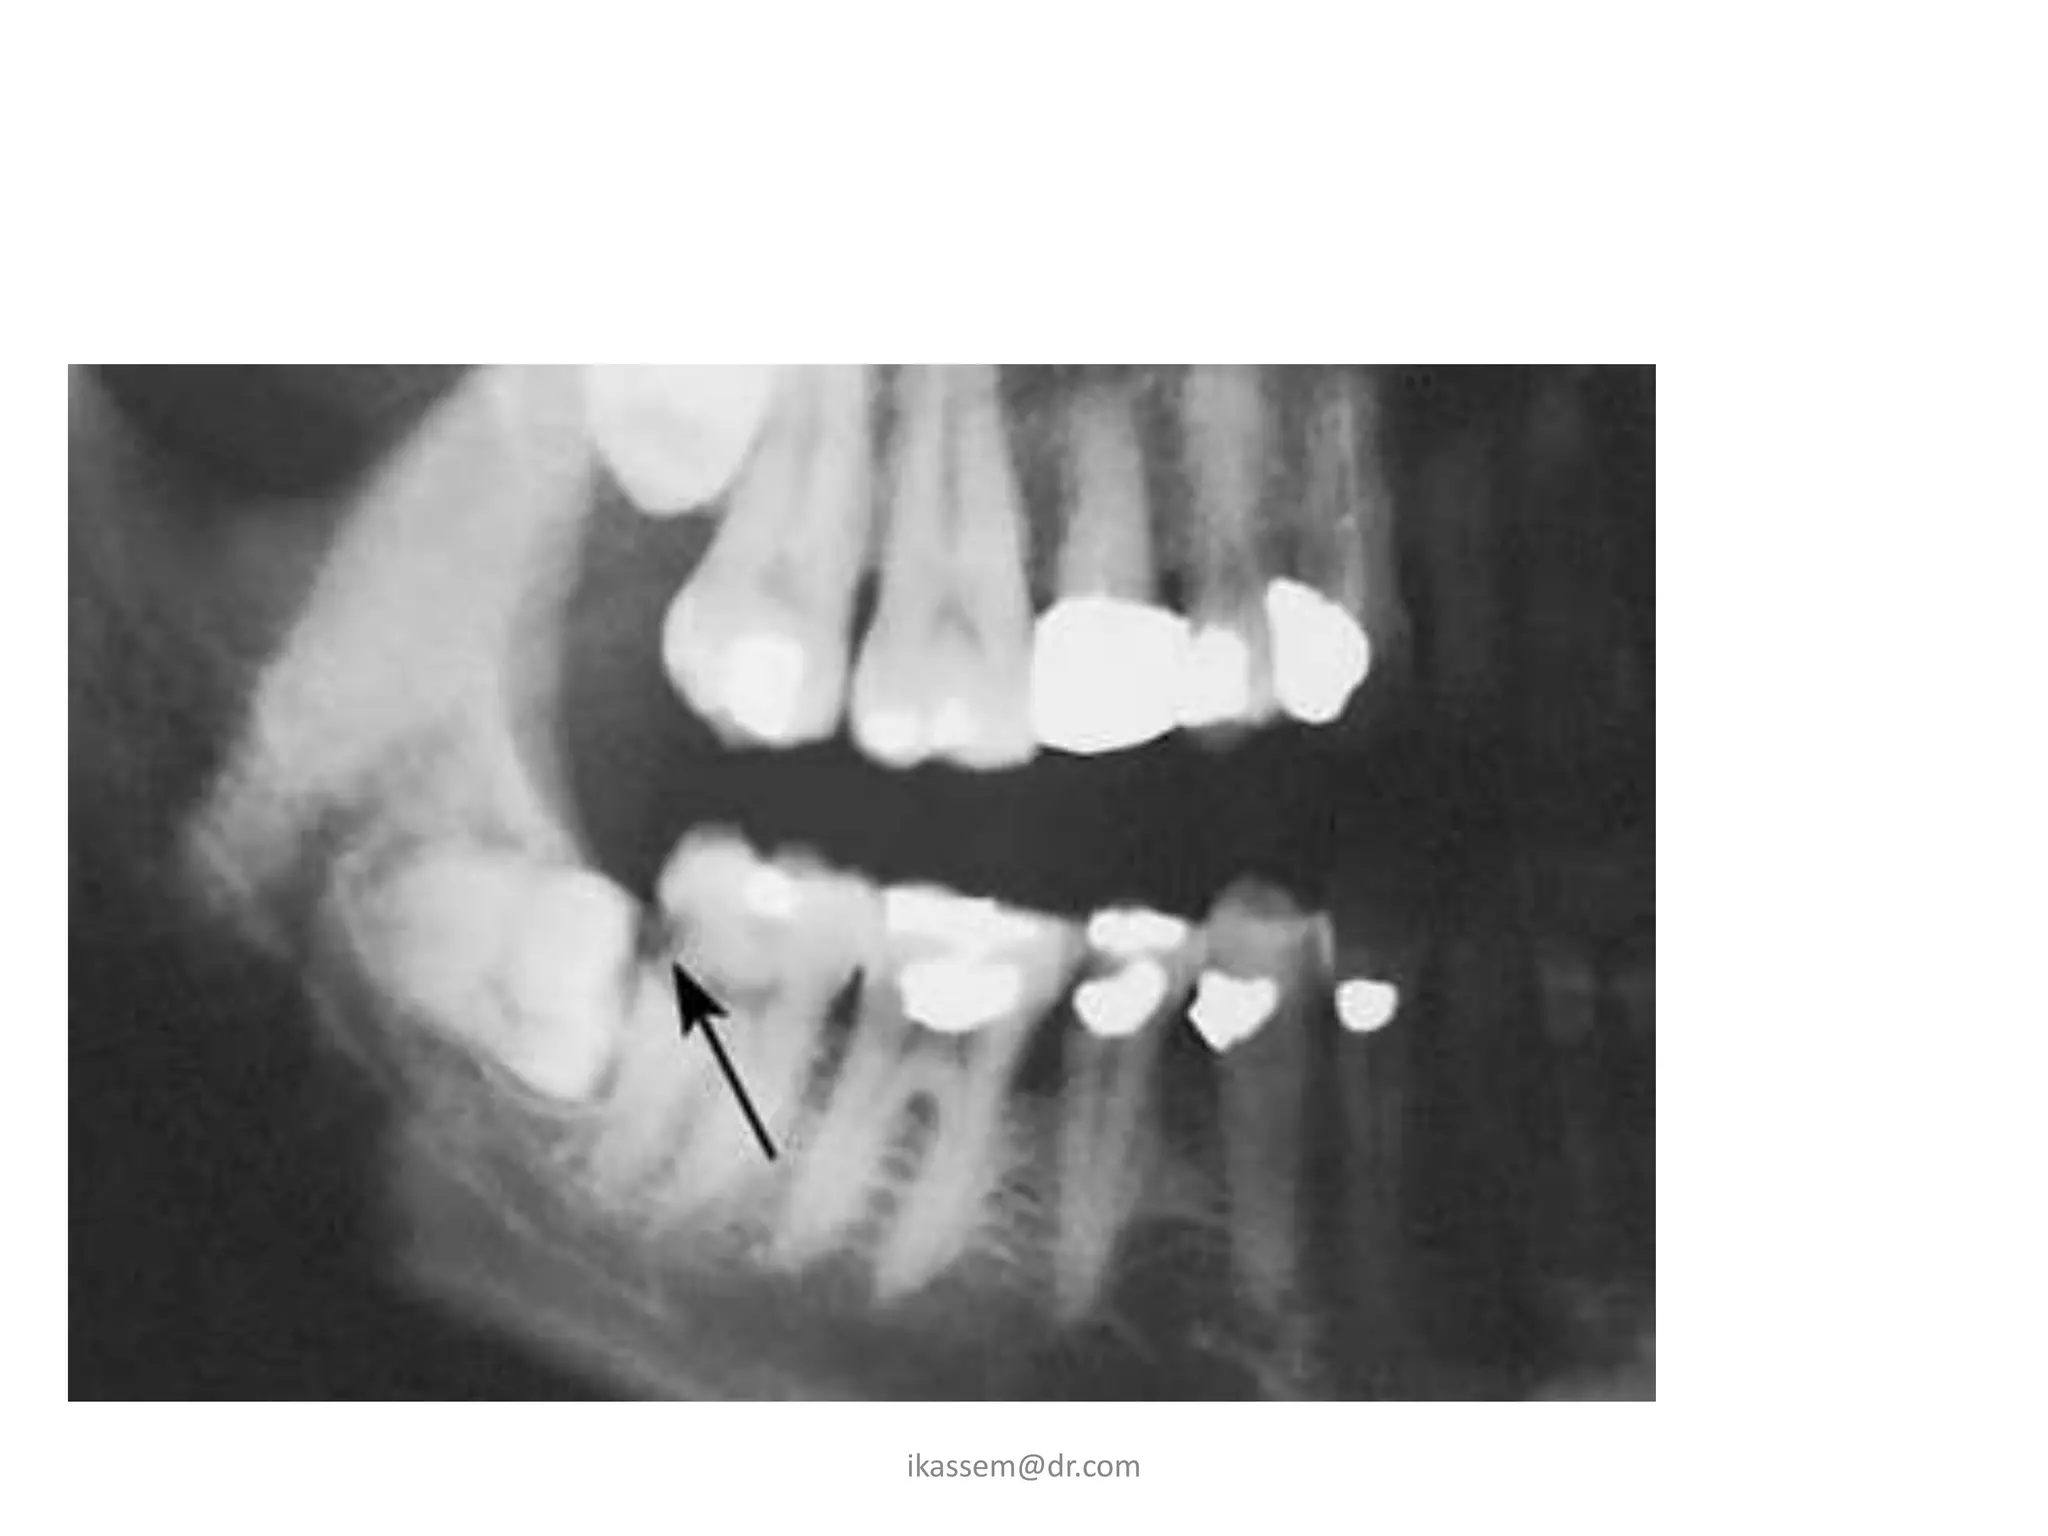

B - Relative depth of the third molar in

bone:

- this show the superior inferior

relationship of the tooth in

relation to the occlusal plan. (Pell

& Gregory)

• Position A:

the highest portion of the tooth is on level

with or above the occlusal plane.

• Position B:

the highest portion is below the occlusal

plane but above the cervical margin of the 2nd

molar

• Position C:

the highest point of the tooth is below the

cervical margins of the 2nd molar (deep

impaction)